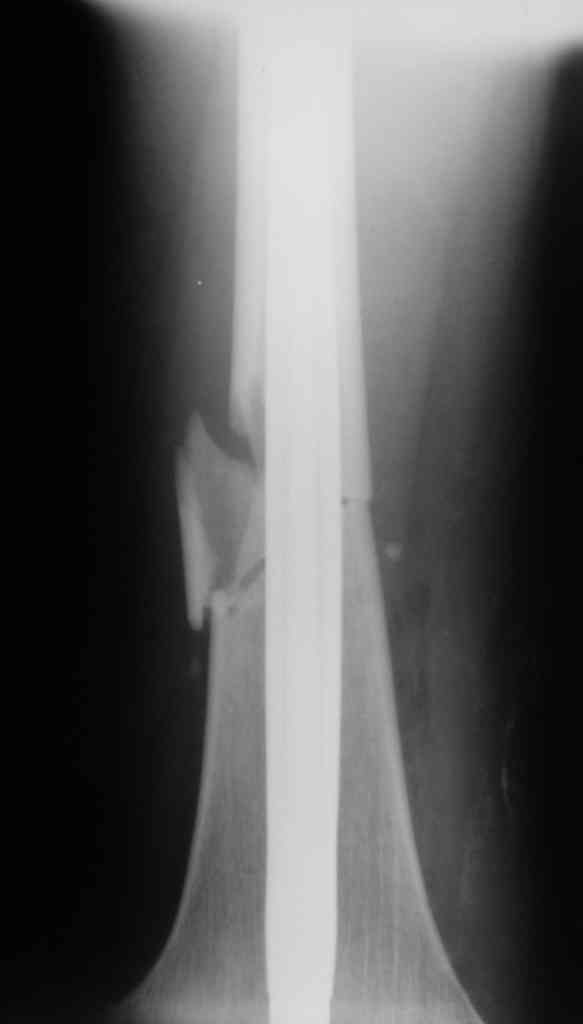

Вчера первый раз синтезировали голень гвоздем Fixion.

Спиральный оскольчатый перелом, ниже середины, у молодого парня. Сделали "классический" вариант гвоздя, который еще без винтов. Получилось все легко. Не торопясь, сделали операцию минут за 20. См. фото.

В отношении ранней нагрузки при спиральных переломах лучше не торопиться. По данному случаю необходимо достигнуть исчезновения щели между штифтом и внутреним кортексом по Rg. А так картинка прекрасная - и длина сегмента и репозиция. Можно поздравить, коллега!